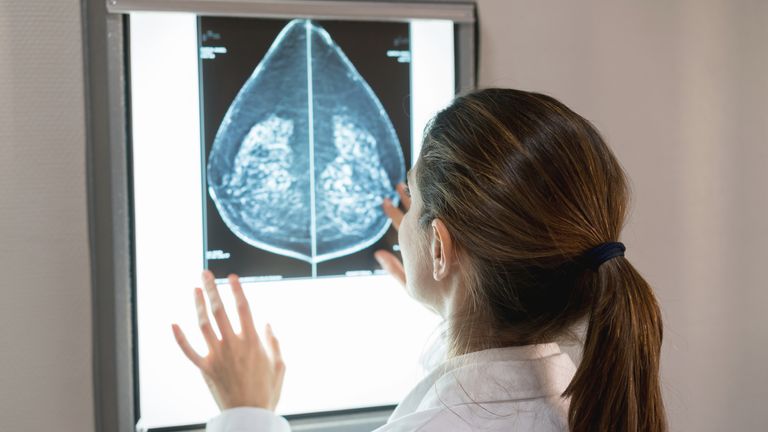

The study, published today by Google, the NHS and Imperial College London, took 115,000 breast scans from five NHS screening services and asked an AI and a human specialist to go through them, looking for cancer.

Significantly, it also detected 25% of “interval cancers’ – cancers diagnosed between routine screening rounds after an earlier scan came up clear – which implies it could help catch breast cancer earlier, a crucial factor in preventing its spread.

Although the AI outperformed a single human, it’s not correct to say it can beat radiologists, because the NHS uses two doctors to go through scans, with a third expert on hand to decide a difference of opinion, a system known as arbitration.